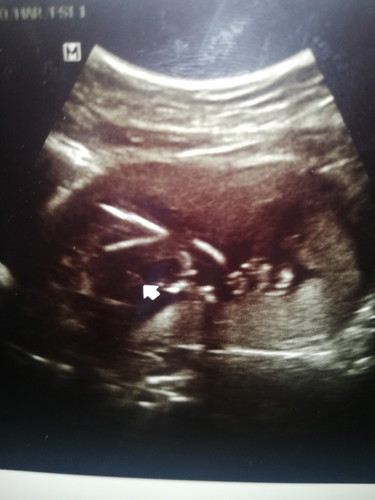

ไปซาวน์เองที่คลินิกเพราะอยากฟังเสียงหัวใจลูก❤️อยากรู้วีคของลูกที่แน่ชัดเพราะไม่มั่นใจวันที่ปจด.มาวันแรกของครั้งสุดท้าย เพราะฝากที่อนามัย รพ.รัฐเขาไม่ซาวน์ให้หรืออาจดูว่าคำนวนที่เราบอกวันปจด.ไปยังดูวีคน้อยอยู่ แต่เห็นแม่หลายบ้านโพสต์ว่าซาวน์ไม่เจอตัวลูกบ้าง ลูกหัวใจไม่เต้นบ้าง แม่บ้านนี้เลยกังวลด้วยเพราะว่าท้องแรกแล้วปล่อยมานานมากกว่าจะมา? ตอนแรกตอนนั่งคุยกะหมอที่คลินิกที่จะไปซว าวน์หมอถามทำไมอยากซาวน์เพราะหมอดูสมุกชมพูที่เราเอาไปด้วยเลยตอบว่าอยากเห็นอยากรู้เสียงหัวใจลูกค่ะ พอซาวน์เท่านั้นล่ะจ้า ตัวเบ่อเริ่มเลย? สรุปน่าจะจำวันของปจด.ผิด จากที่ตรวจคาคะเนคลอด4 ธ.ค. 63 เลื่อนมาเป็น 7 พ.ย. 63 เลยจ้า มาเกือบครึ่งทางแล้วน๊า ดีใจมากๆเลยตอนซาวน์แล้วเห็นลูกดิ้น หัวใจเต้น แล้วยังเห็นเพศชัดเจนเลยจ้า บ้านนี้ไม่อายให้เห็นครั้งแรกที่ซาวน์เลย❤️